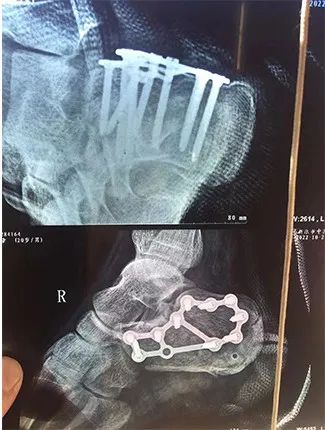

足跟粉碎性骨折

被植入多根鋼釘